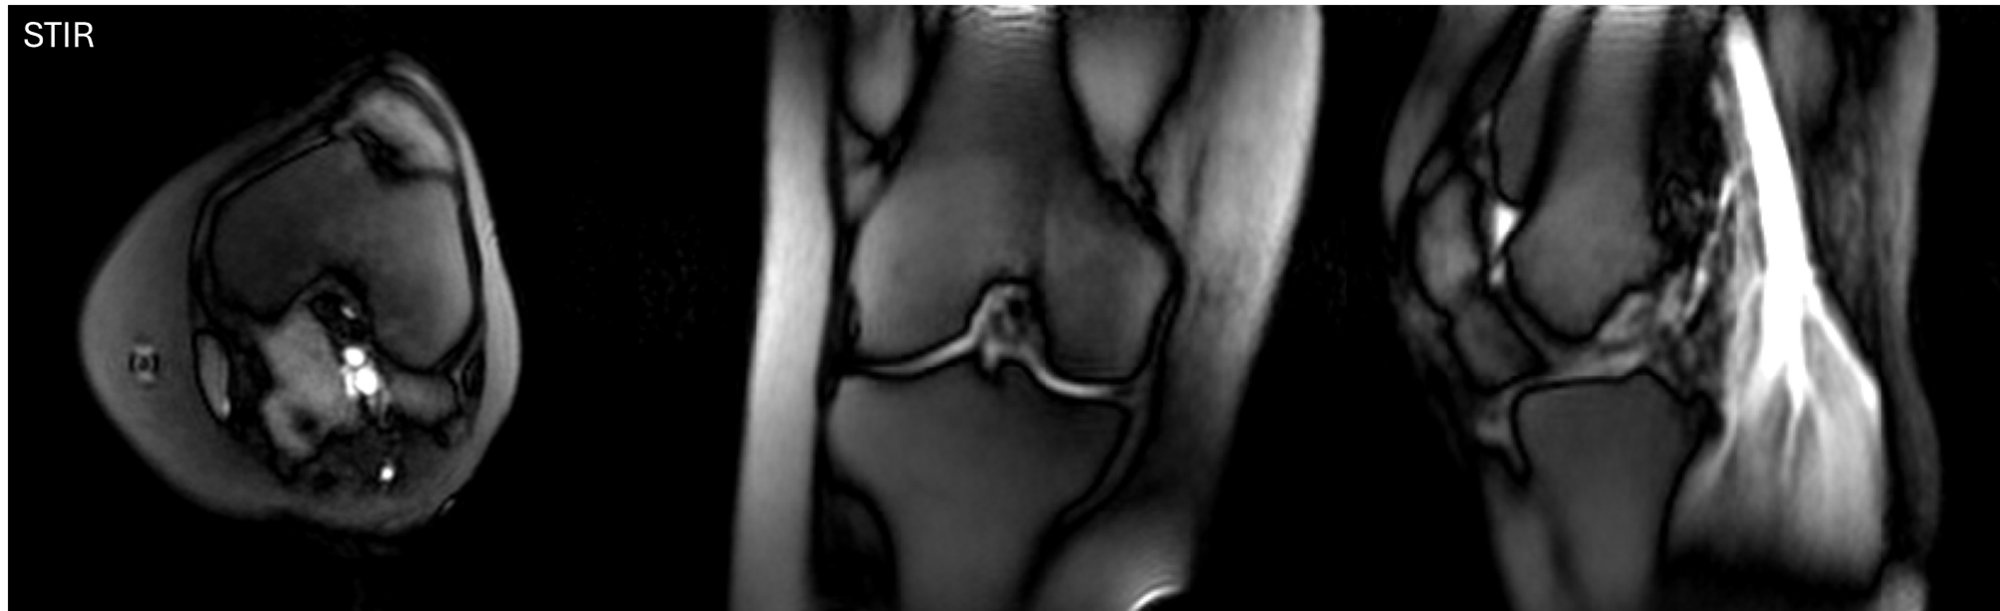

Knee Image

Clear visualization of ligaments, menisci, and articular cartilage enables accurate diagnosis of traumatic injuries and degenerative conditions. The system’s portable nature allows point-of-care imaging for sports medicine applications.